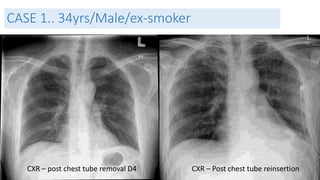

CASE 1.. 34yrs/Male/ex-smoker

CXR – post chest tube removal D4 CXR – Post chest tube reinsertion

Management and Outcome

• Diagnosis:

• Primary spontaneous pneumothorax

• Management

• Chest Tube insertion

• Gumco suction D2

• Chest tube removal on D4 and reinsertion due to recurrence ( persistant air

leak)

• VATS ( Video assisted thoracosopic surgery)

• Outcome

• Discharged well on D2 post op.

• Lung fully expanded and asymptomatic.